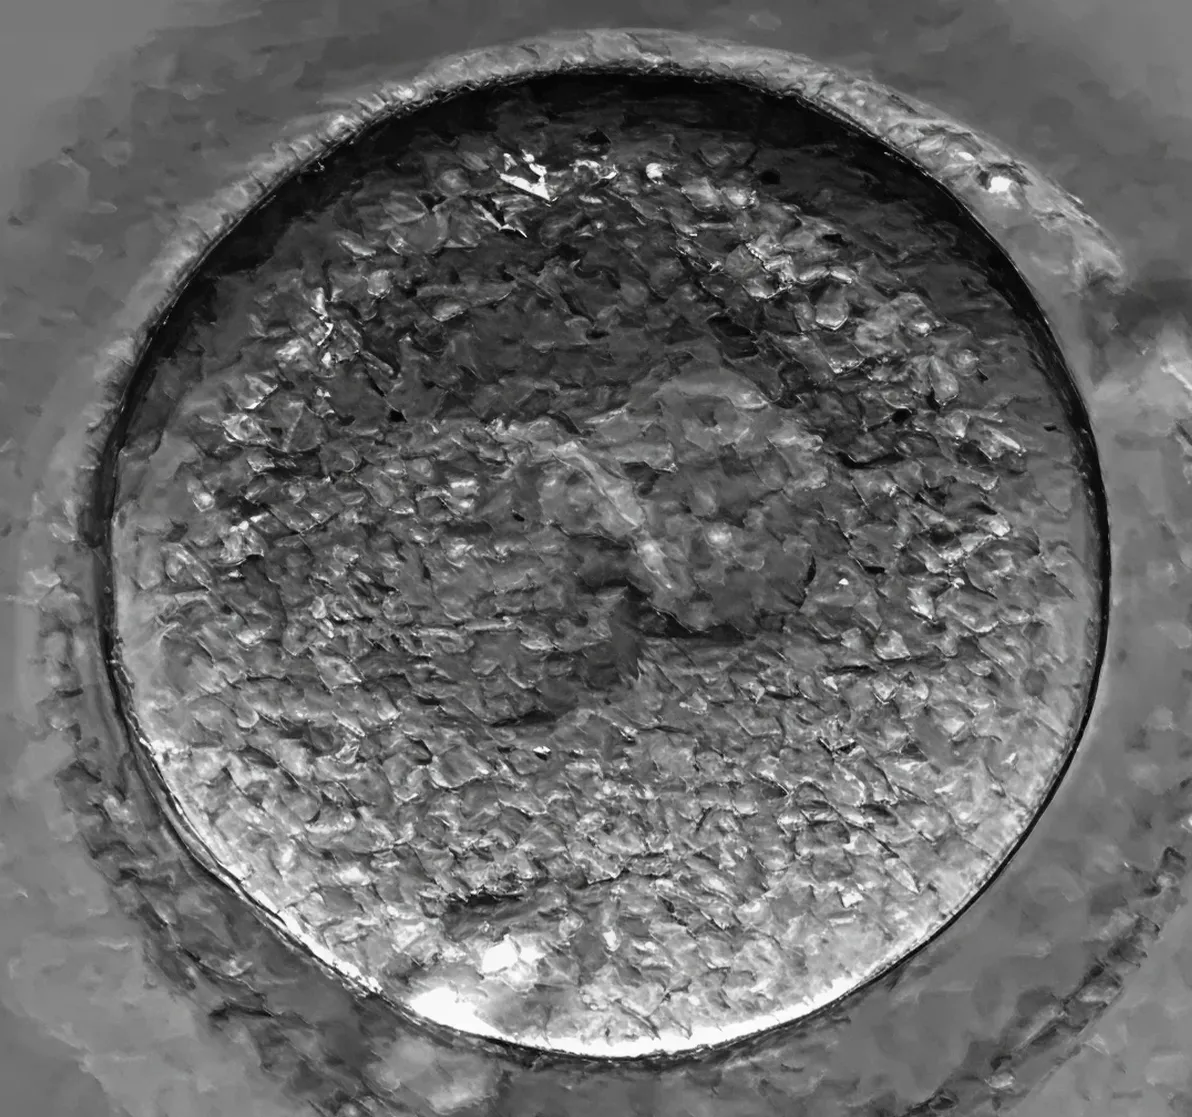

Началото на живота — оплождането

След оплождането започва едно удивително пътешествие — превръщането на оплодената яйцеклетка в ембрион, готов за имплантация. Нормално оплодената яйцеклетка има два пронуклеуса – единият от майката, а другият – от бащата. Това е началото на нов живот, който вече носи уникален генетичен код.

Какво се вижда? – На екрана се вижда една голяма кръгла клетка с две ясно различими проядра – това е знак, че оплождането е настъпило успешно. Тези две проядра съдържат генетичната информация на майката и бащата и скоро ще се слеят в една обща клетка – зигота.